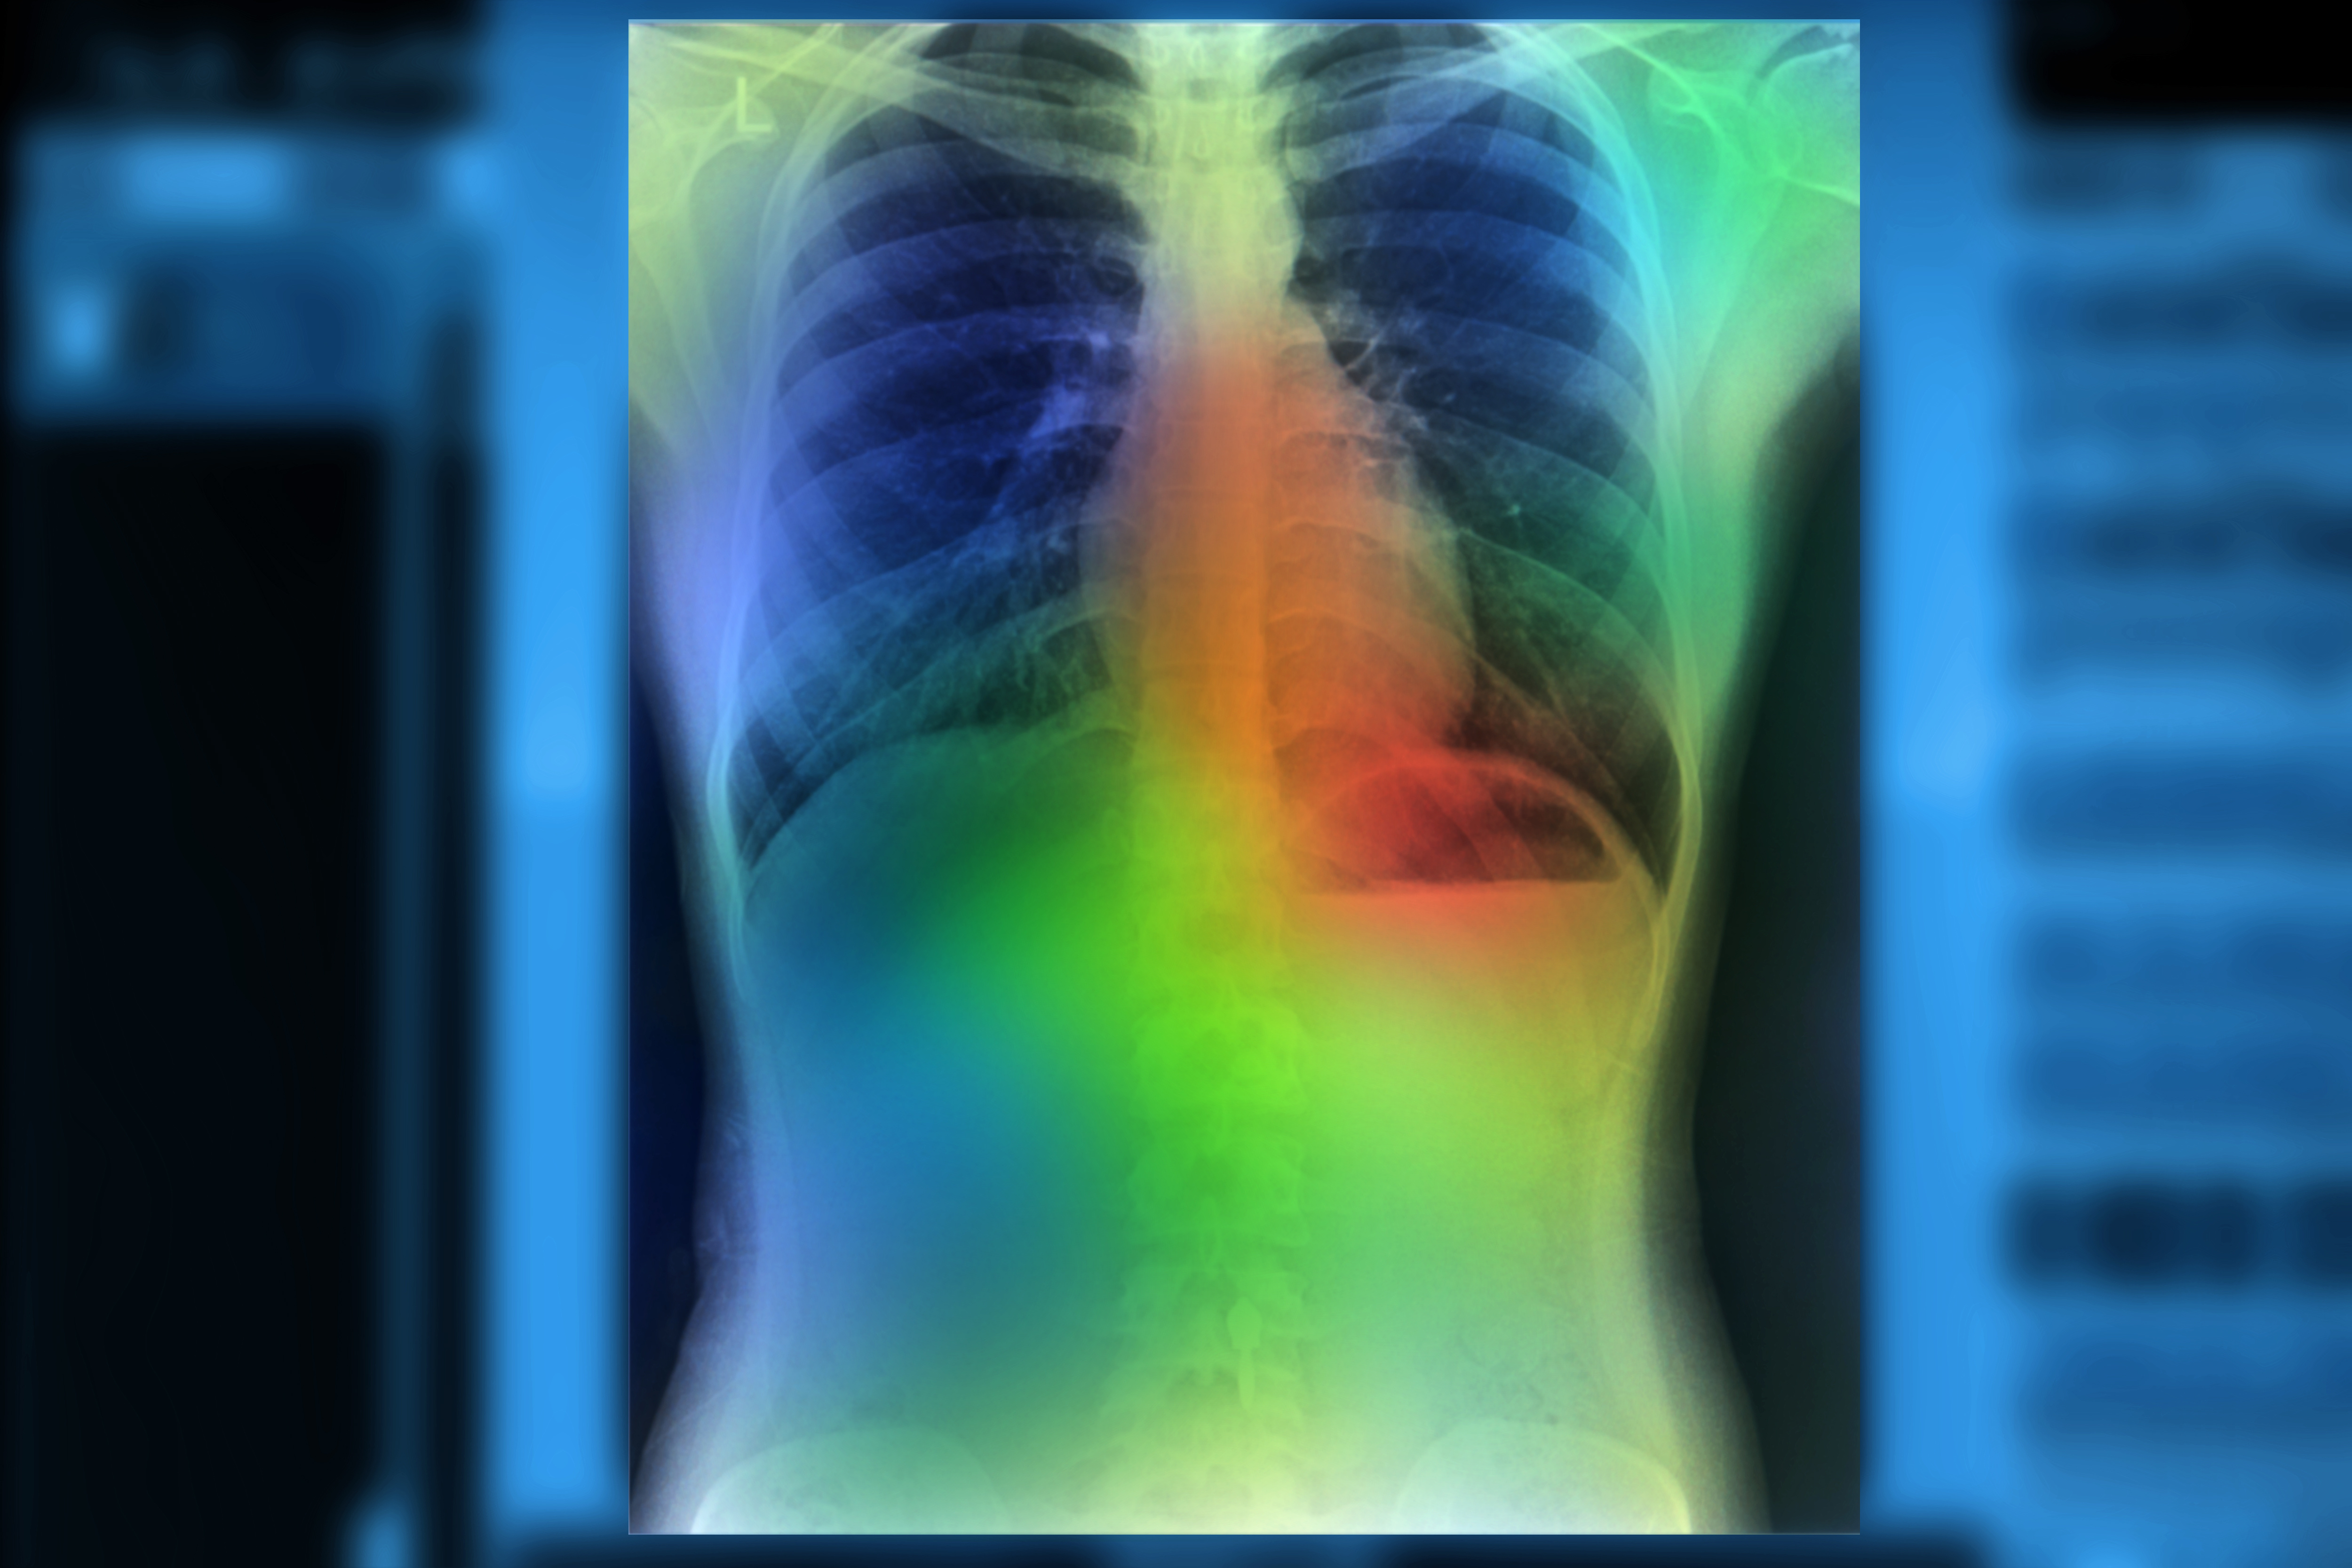

Original CT scan (left) and overlay (heat map; right) of disease areas in the lungs of a CF patient and healthy control, determined in several seconds by Thirona's new Pragma-AI software. Image courtesy of Thirona.With Pragma-AI, Thirona has automated the method so that analysis of CT scans of cystic fibrosis patients can be performed in several seconds without human interference, the company stated.